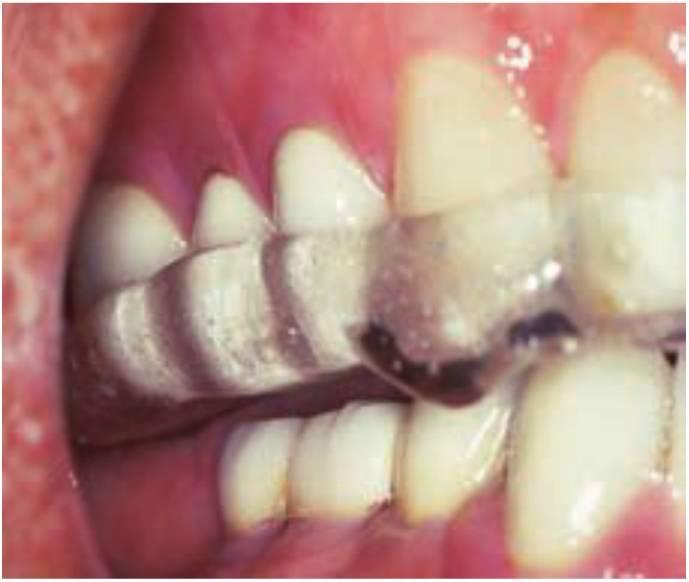

El desgaste cervical es, principalmente, un signo de las parafunciones de bruxismo o apretamiento (fig. 6-10).

Anteriormente, Black analizó las ocho teorías más populares sobre la recesión de encía en los dientes, encontrándolas todas inconcluyentes. Esta situación se ha denominado frecuentemente como «abrasión por el cepillo de dientes». McCoy en contró esta condición en uno de cada dos dientes, en un solo diente e incluso en los dientes de algunos an imales. La parafunción era la característica común entre los pacientes que la presentaban. La imagen de corte de la porción cervical de los dientes se correlaciona directamente con la concentración de fuerzas demostradas en el análisis finito tridimension al y en estudios de fotoelasticidad. La abfracción de los dientes también se observó en gatos, ratas y marmotas y ya se describió en la literatura en 1930. Un estudio sobre la población mayor no institucionalizada reveló que la abrasión cervical estaba presente en un 56 % de los participantes.

Otros signos de fatiga de esmalte o del material de oclusión relacionados con el bruxismo y el apretamiento incluyen las invaginaciones oclusales o fosas, líneas de estrés en el esmalte, líneas de estrés en reconstrucciones con aleaciones o acrílicas (líneas de Luder) y la fractura del material (figs. 6-11 y 6-12).

El fremitus se puede llegar a ver clínicamente en muchos dientes con erosiones cervicales y sin movilidad. No todas las erosiones gingivales son provocadas por una parafunción. Sin embargo, cuando aparezca se debe evaluar con especial atención la oclusión junto con otros signos de fuerza excesiva. Si se concluye que las fuerzas excesivas son la causa, se denomina esta condición como abfracción cervical.